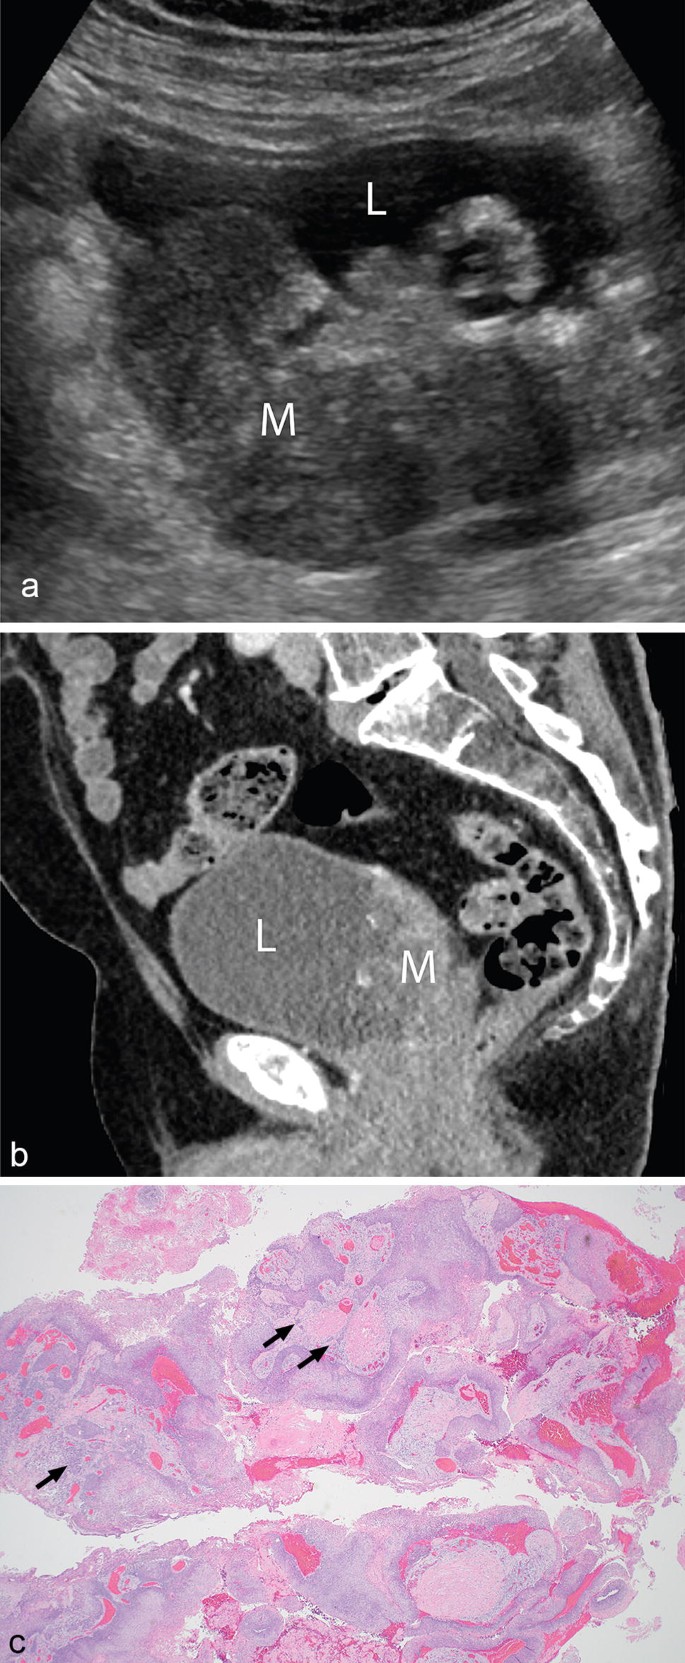

View Squamous Cell Carcinoma Bladder Ultrasound UK. Squamous cell carcinoma of the urinary bladder is a malignant neoplasm derived from bladder urothelium with pure squamous phenotype. Squamous cell carcinomas (sccs), also known as epidermoid carcinomas, comprise a number of different types of cancer that result from squamous cells.

Squamous cell carcinoma is a common skin cancer that usually looks like a red bump or a scaly sore. Squamous cell carcinoma is a cancer of the skin that generally appears as a thin, flat cell on the outer layer of the skin. Urothelial carcinoma (transitional cell carcinoma):

1, 2, 3 this malignancy is essentially similar to the tumors arising in other organs.